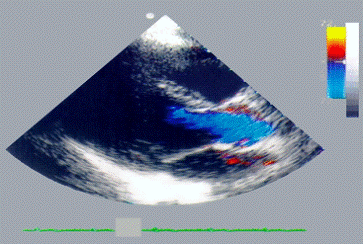

Рис. 6б). Двухмерная цветная допплер-эхокардиограмма с изображением сердца в проекции длинной оси: в период систолы, синий цвет указывает направление потока крови от датчика, поток соответствует изгнанию крови из левого желудочка. Справа от эхокардиограммы видна цветовая шкала потоков и шкала акустической плотности

Рис. 6а). Двухмерная цветная допплер-эхокардиограмма с изображением сердца в проекции длинной оси: в период диастолы, красный цвет указывает направление потока крови в сторону датчика, поток соответствует фазе быстрого наполнения левого желудочка. Справа от эхокардиограммы видна цветовая шкала потоков и шкала акустической плотности